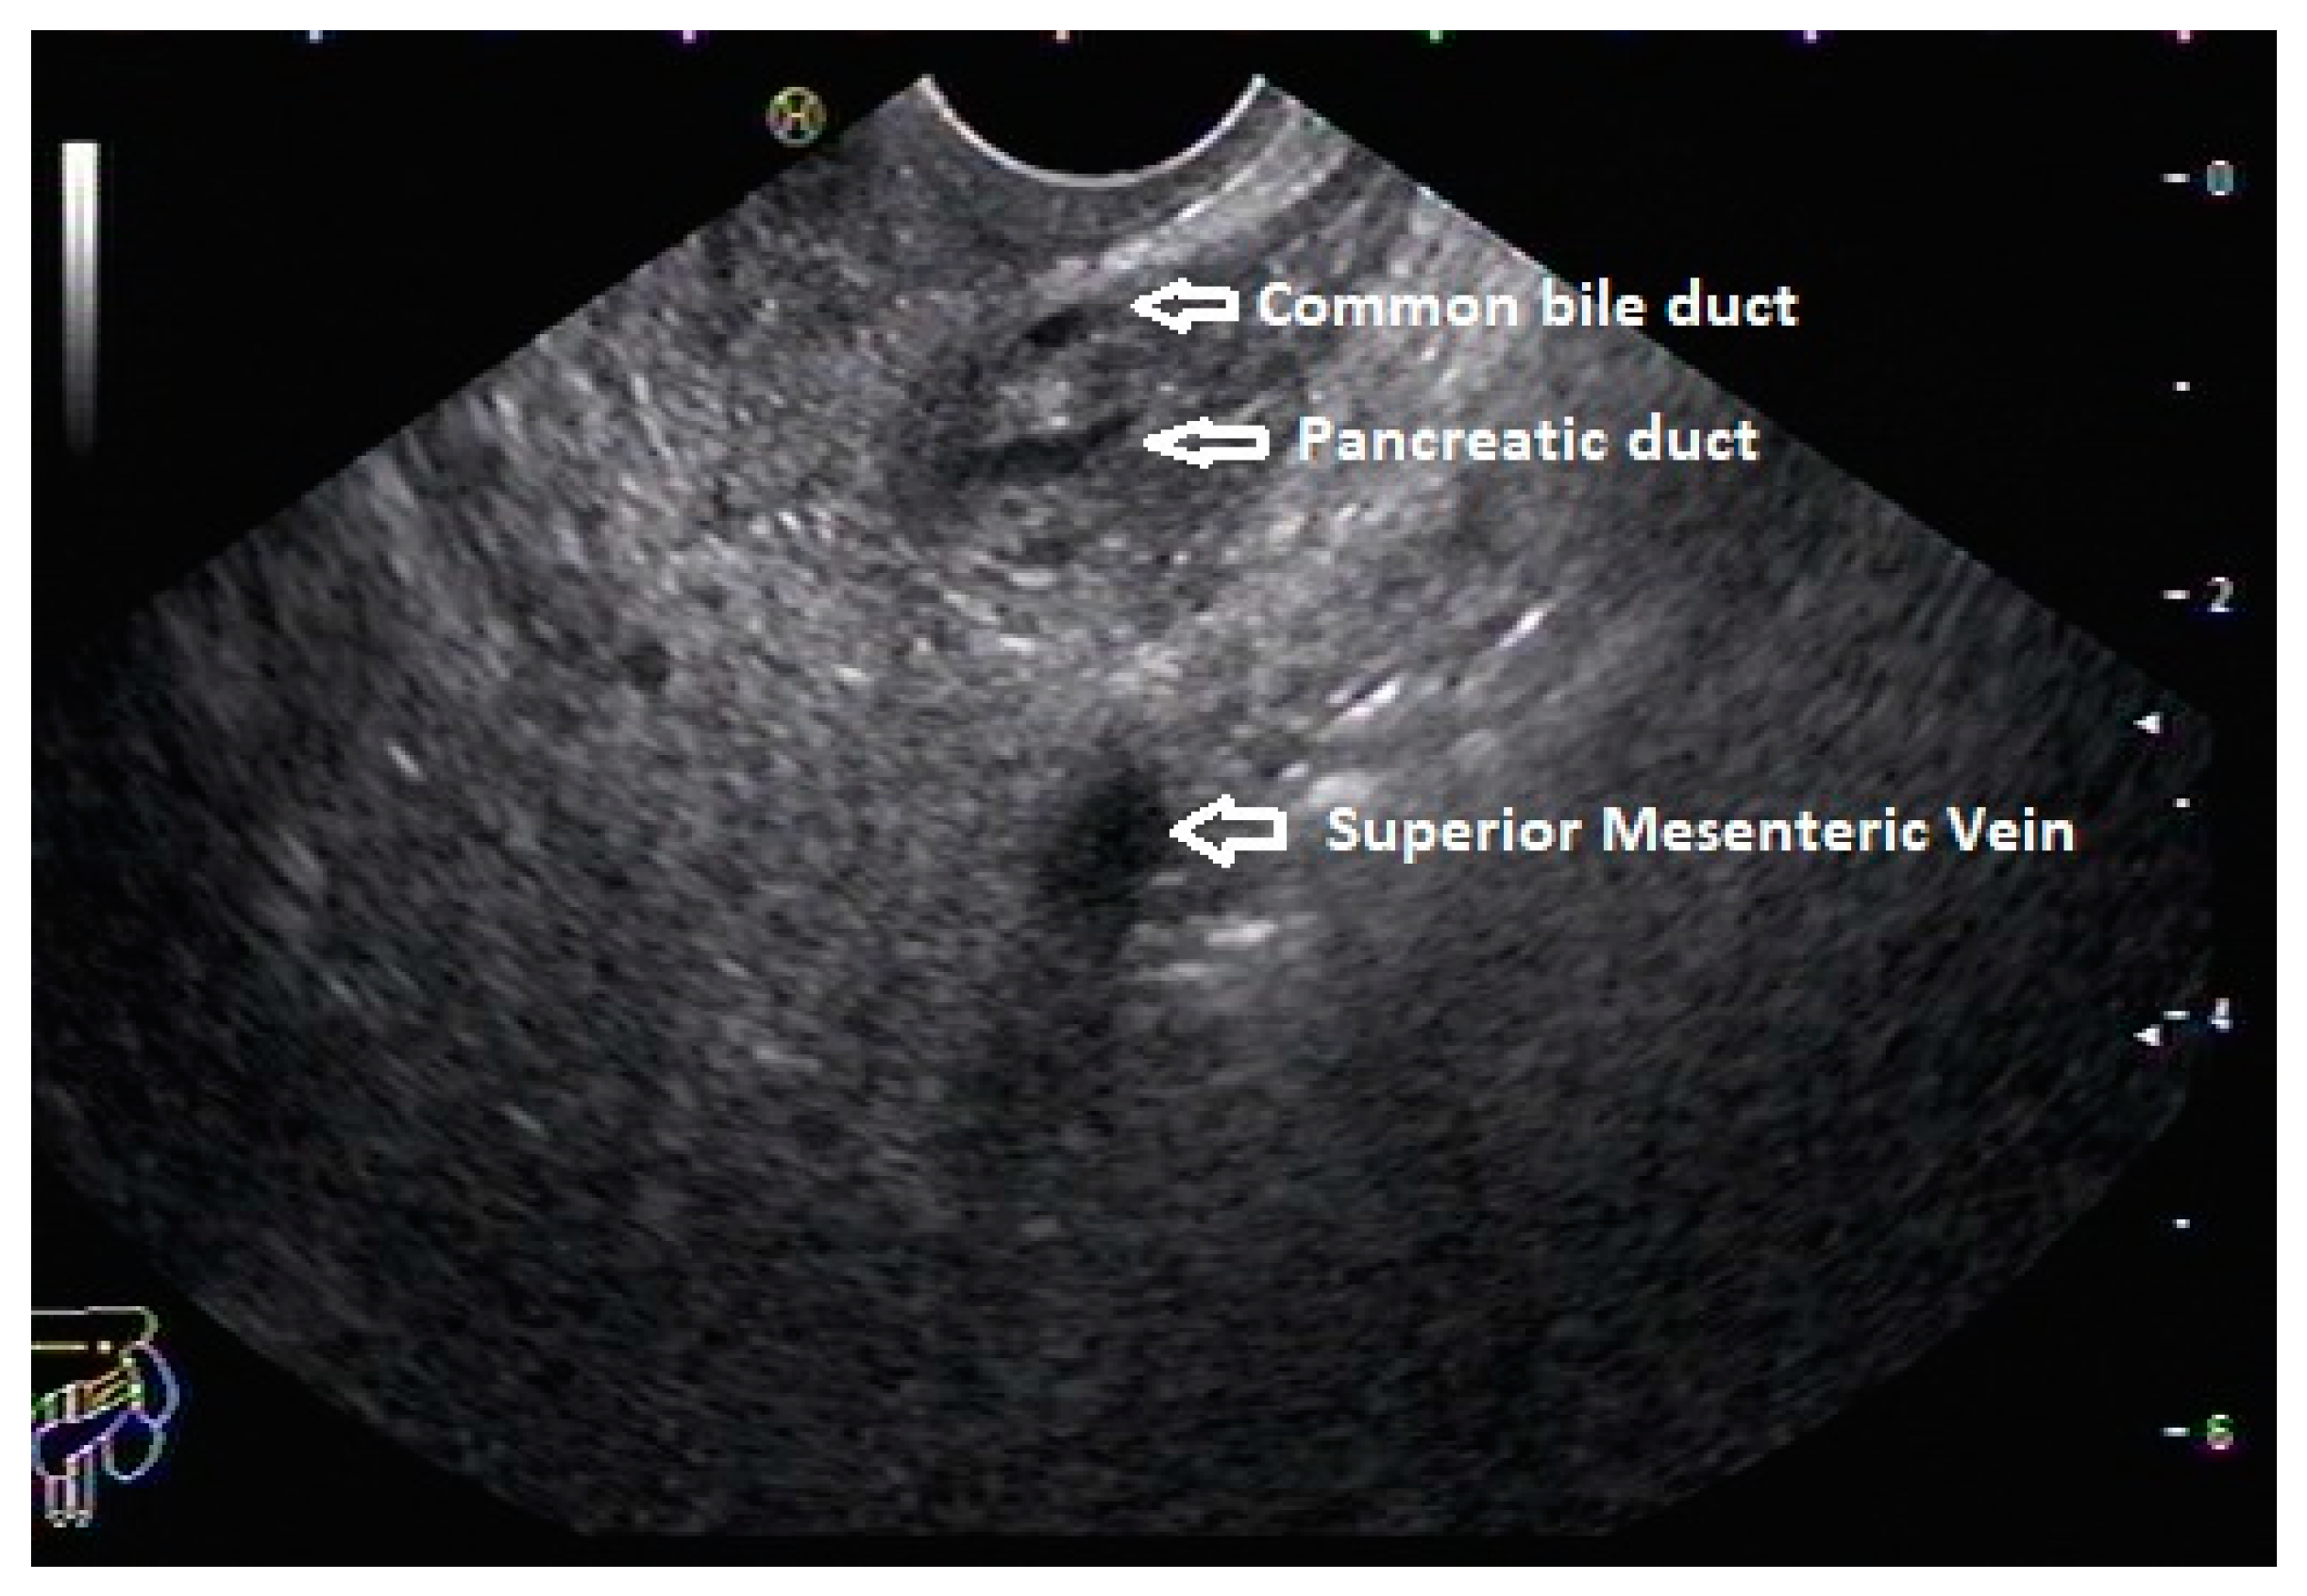

In routine endosonographic examinations, all parts of the pancreas are comprehensively examined when seen from three stations: the apex of the duodenal bulb, papilla, and distal to the papilla. Among these, the best position is the apex of the duodenal bulb as it brings the major portion of the head of the pancreas, distal common bile duct, and portal vein in the same frame. For positioning, the EUS scope is advanced along the greater curvature of the stomach and when pylorus is visible, the tip of the scope is negotiated through it, followed by air insufflation of the duodenal bulb. This is followed by gentle downward deflection of the tip of the scope, making the duodenal bulb visible. Doppler imaging helps differentiating bile duct from the arteries (the hepatic artery and gastroduodenal artery) and the portal vein. At this point, the endosonologist gets the view of the distal CBD, pancreatic duct, and portal vein in a single frame in which one structure appears to lie on top of the other, and this is called the stack sign (Figure 1). Absence of the stack sign suggests the possibility of pancreas divisum (Figure 2). As these structures do not lie in the same plane, various maneuvers like clockwise and counter-clockwise rotation and right and left torque are required for a detailed examination of these structures [12]. Although this sign is conventionally described in radial EUS, linear EUS can also detect similar anatomical configuration, although there are some subtle differences in linear EUS. In linear EUS, usually, the “stack” consists of the distal CBD and pancreatic duct, which are seen on a parallel axis (the portal vein is not seen). However, the superior mesenteric vein (SMV) or artery (SMA) can be seen on linear EUS on a different axis, once a clockwise rotation is performed, and the origin of the portal vein from the SMV can also be easily demonstrated (Figure 3) [27].

Figure 1.

Radial EUS showing both ventral pancreatic duct and common bile duct stacked together. This finding rules out pancreas divisum.